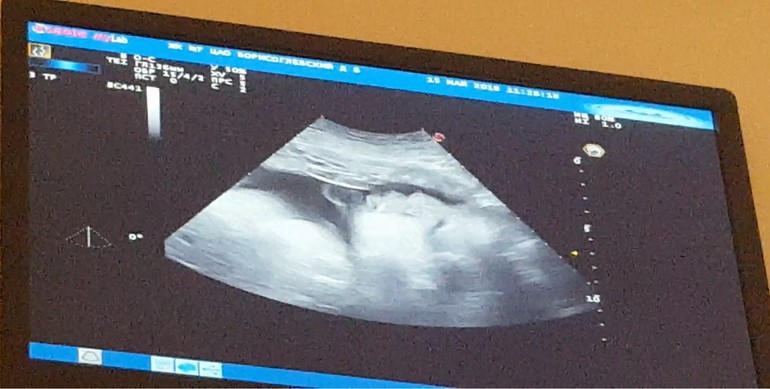

Сегодня ходила на узи, что имеем: по М срок 33+2, вес 2550, рост 45, все в норме, стопа 7см. Лежит вниз головой. ЧСС 130. Степень зрелости плаценты 1. Шейка 30мм.

Наше фото

Какая масенькая на фото. Как все таки мало им потом место)